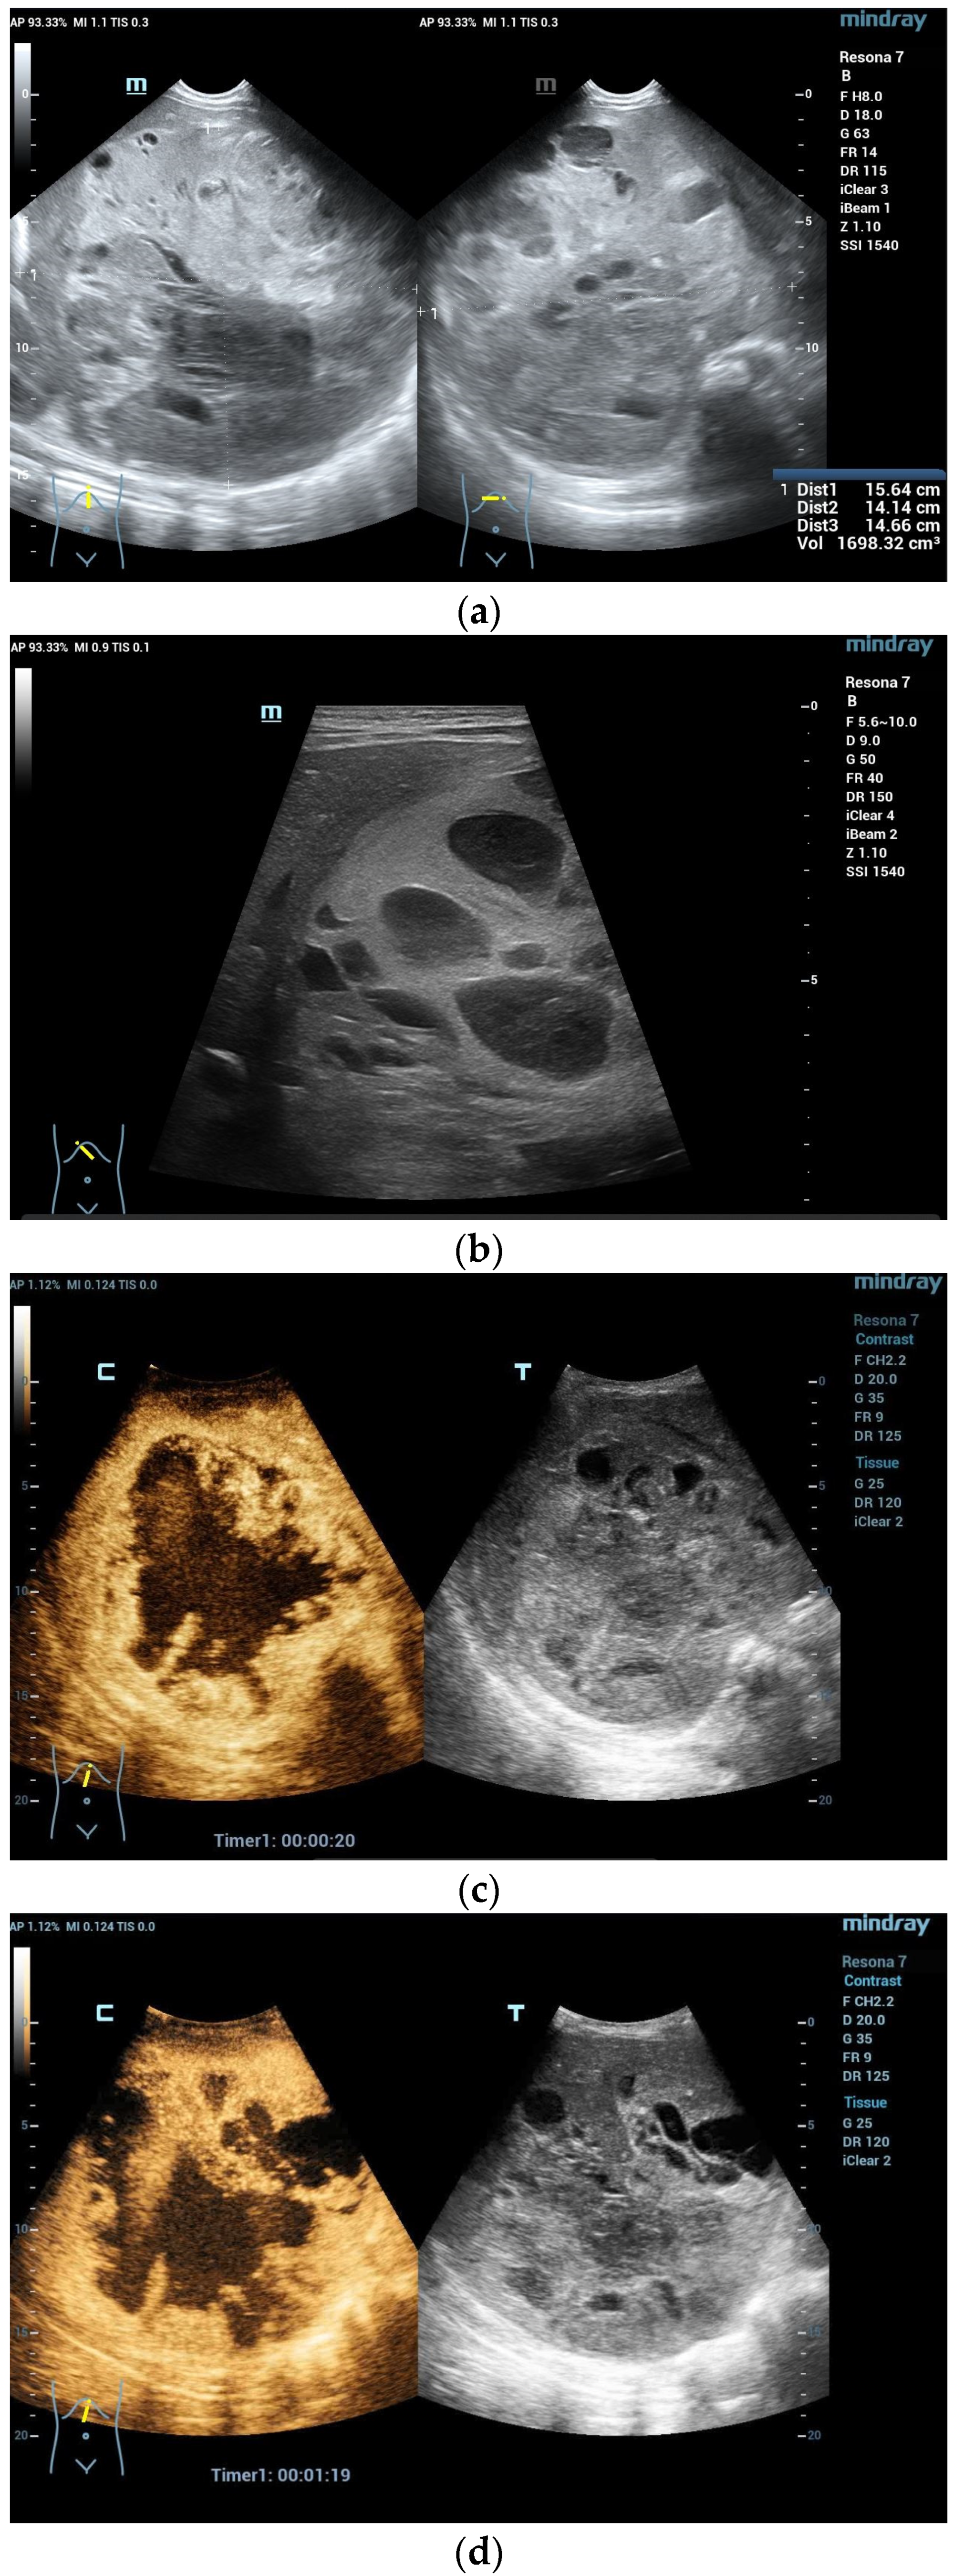

CEUS: HAS is characterized predominantly by nodular peripheral enhancement during the arterial phase and portal venous phase, while diffuse chaotic or reticular enhancement could also be seen. In the late phase, HAS typically shows hypoenhancement, possibly with partial rim-like enhancement or isoenhancement, without centripetal filling [10]. In contrast, typical hemangiomas could be accurately diagnosed by CEUS with peripheral nodular enhancement and centripetal filling, which should be differentiated from HAS (Figure 4).

Figure 4.

A 17-year-old female with a focal liver lesion in the right liver lobe and a small oval cyst in the surrounding area (a). Arterial phase hyperenhancement predominantly in the periphery with a rim and septae-like structures with non-enhancing areas (b) and washout are documented (c). Needle biopsy with histological evaluation revealed angiosarcoma of the liver.